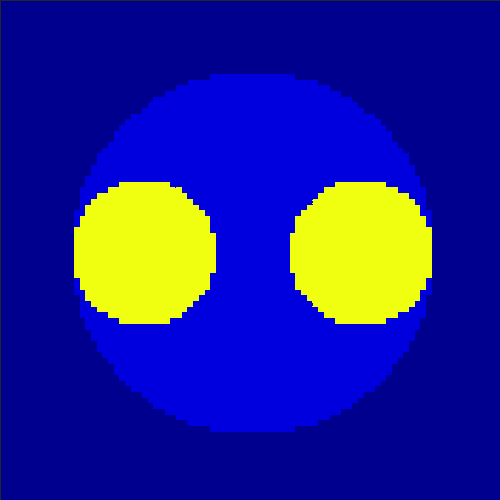

The first data set consists of a heart-shaped region and three circles on a static background (see figure 1 (a)). The two smaller circles are assumed to belong to

the same tissue type and therefore to the same subregion, which causes a total of four subregions, including the background. To simulate a more realistic application of dynamic SPECT

imaging, we used a synthesized representation of a rat liver as a second data set (see figure 1 (b)). The temporal concentration curves used to simulate the data sets

are shown in figure 2. As before, the total number of subregions was chosen to be equal to four in order to provide a both simple and realistic shape model.